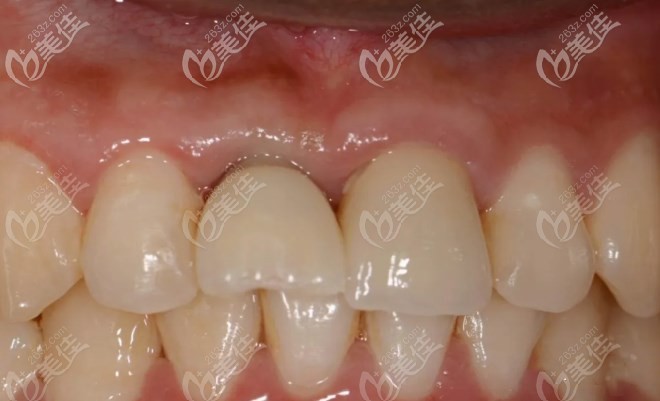

当天种植后戴上临时牙冠的图片:

戴上牙冠后半年后复查:

你能看出来哪个是假牙吗?从图片可以看出种植牙不仅满足了和自然牙齿一样功能性还有美观性。